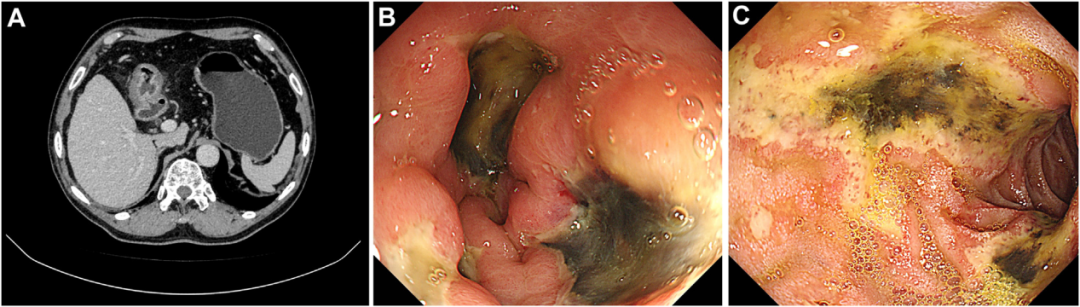

- 【论著】粪钙卫蛋白在溃疡性结肠炎内镜活动度评估中的价值及与常用炎症指标的比较分析 溃疡性结肠炎(ulcerative colitis,UC)是一种慢性复发性的肠道炎性疾病。随着 UC 的疾病进展,患者常出现营养不良、贫血等并发症,严重影响患者的生活质量。……